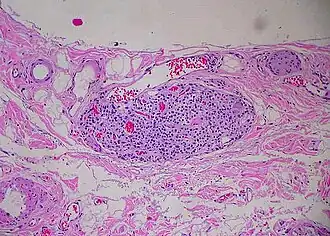

Paraganglion of gallbladder

A paraganglion (pl. paraganglia) is a group of non-neuronal cells derived of the neural crest. They are named for being generally in close proximity to sympathetic ganglia. They are essentially of two types: (1) chromaffin or sympathetic paraganglia made of chromaffin cells and (2) nonchromaffin or parasympathetic paraganglia made of glomus cells. They are neuroendocrine cells, the former with primary endocrine functions and the latter with primary chemoreceptor functions.[1]

Nonchromaffin paraganglia include carotid bodies and aortic bodies, some are distributed in the ear, along the vagus nerve, in the larynx and at various other places.[2]